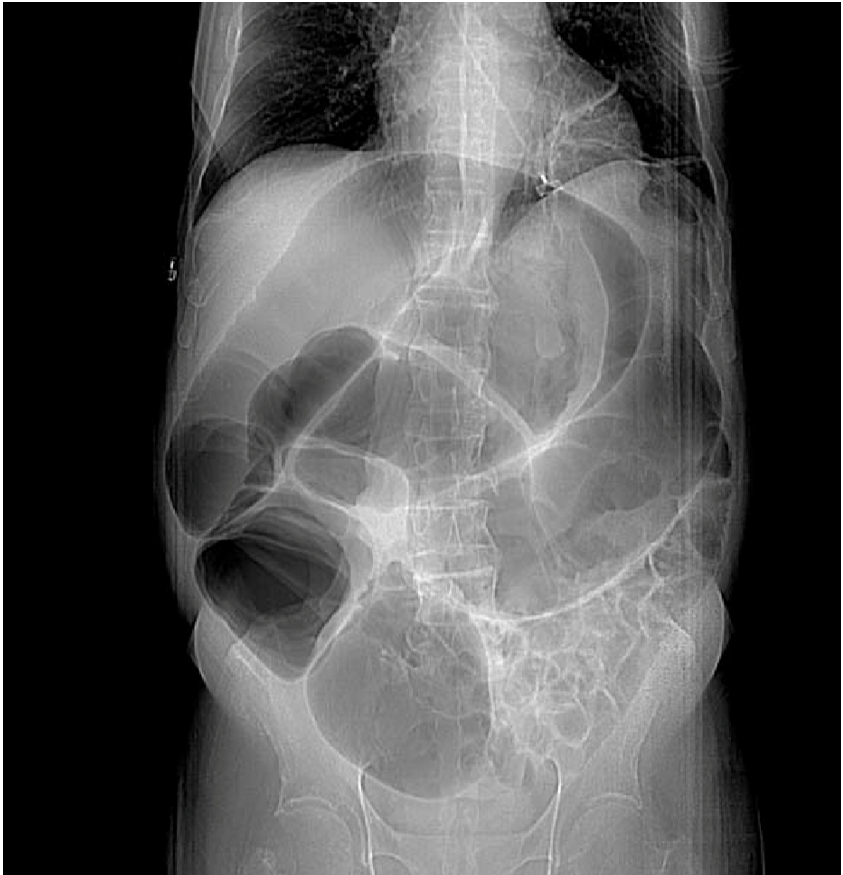

(3) 복부 X선(upright의 경우 다수의 air-fluid level인 step-ladder sign 관찰)

* 장폐색 문제에서 복부 X선 소견이 주어진 경우, 서서 찍은 것인지 누워서 찍은 것인지 사진을 자세히 살펴보면 쓰여있으므로 참고하면 유용하다.